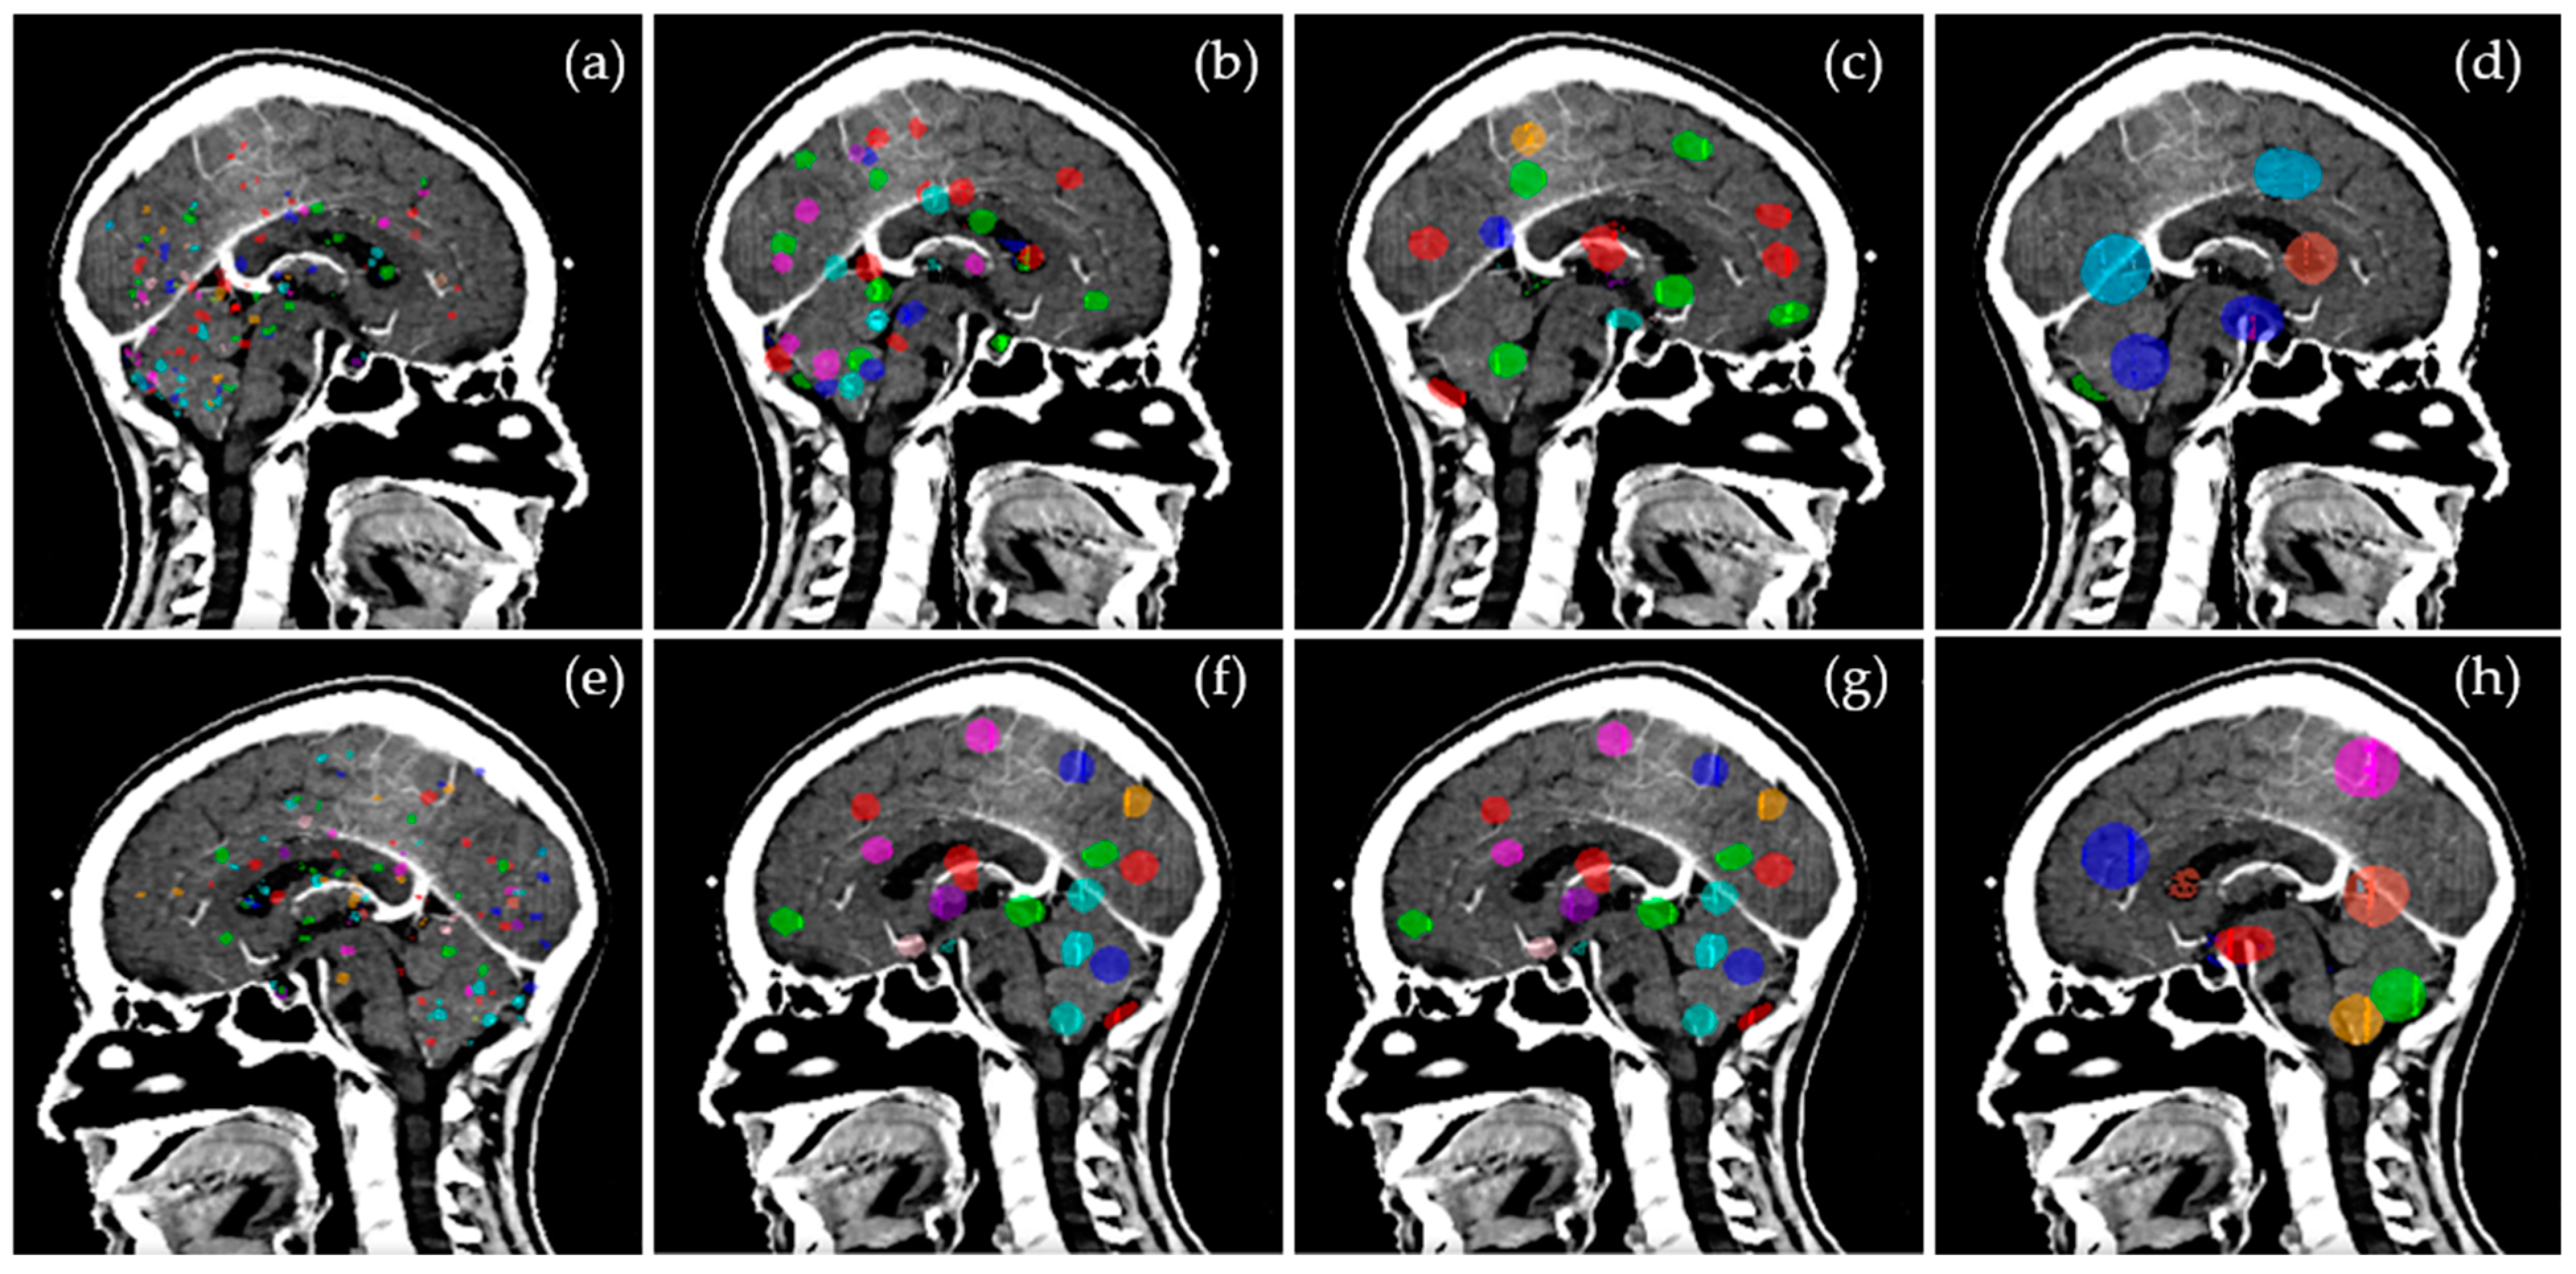

3.1. Target Distribution